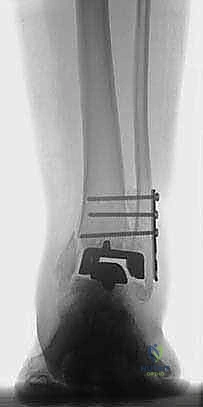

تثبيت مفصل الكاحل الأمامي: حل فعال لخشونة الكاحل المزمنة مع الأستاذ الدكتور محمد هطيف

تعرف على تثبيت مفصل الكاحل الأمامي لعلاج خشونة الكاحل المتقدمة. اكتشف الأعراض، التشخيص، والخطوات الجراحية مع الأستاذ الدكتور محمد هطيف في ص…